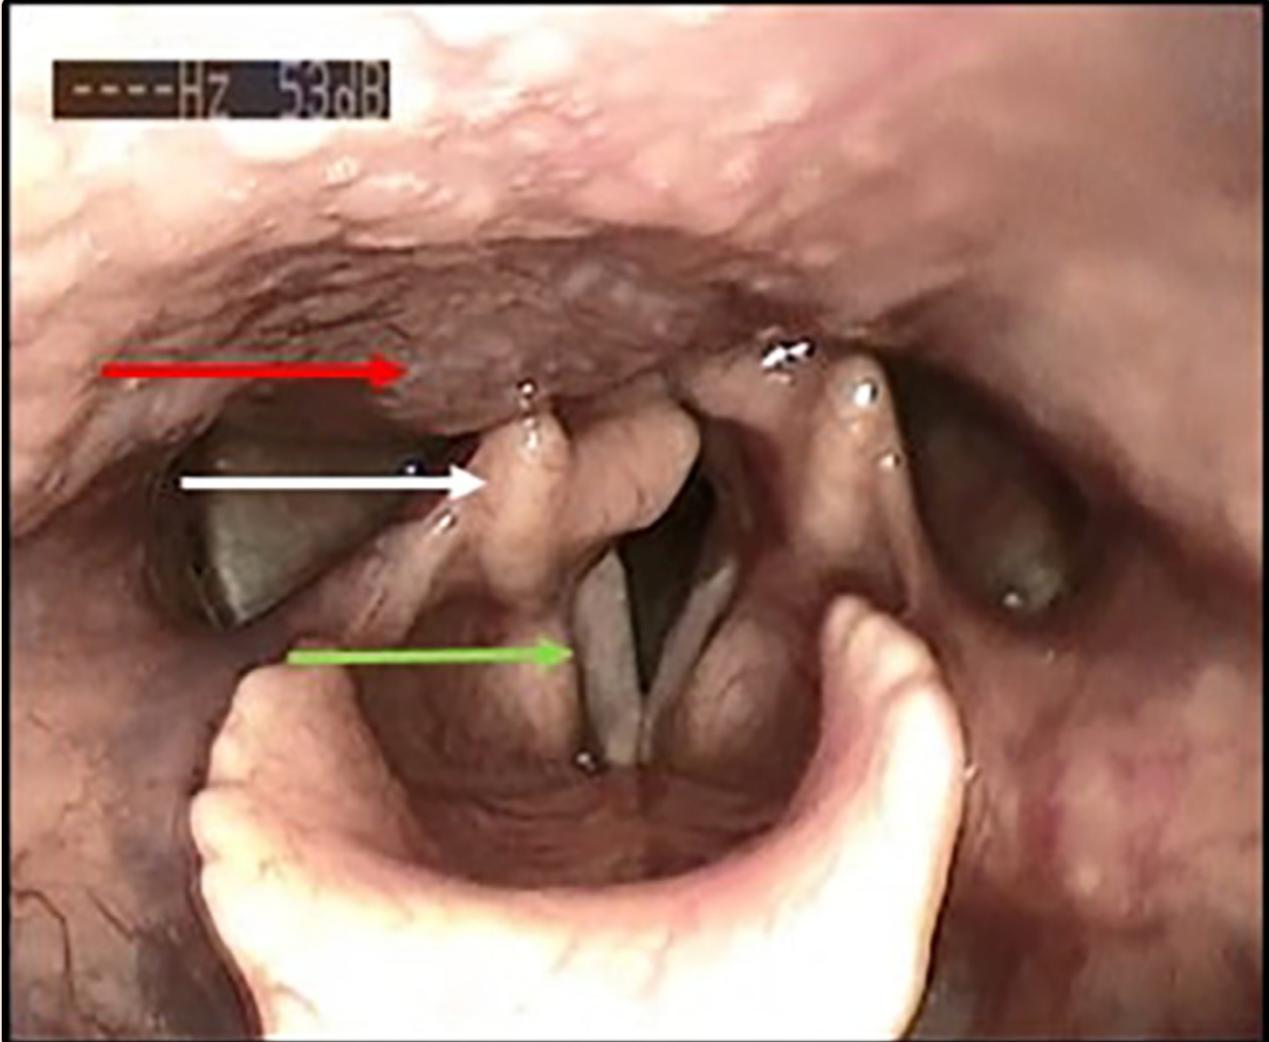

一名72岁的患者因轻微的慢性进行性发音困难就诊,患者诉嗓音的波动影响了他作为教堂歌手的活动。他无吸烟史,否认吞咽困难或咳嗽等其他相关症状。纤维频闪喉镜检查显示一个搏动性环后肿块压迫右侧杓状软骨(图1)。考虑到肿块的搏动性外观,怀疑是颈内动脉的解剖变异。耳鼻喉科余检查均正常。

图1 喉镜检查。咽后壁肿物(红色箭头),压迫右侧杓状软骨(白色箭头),右声带(绿色箭头)无损伤